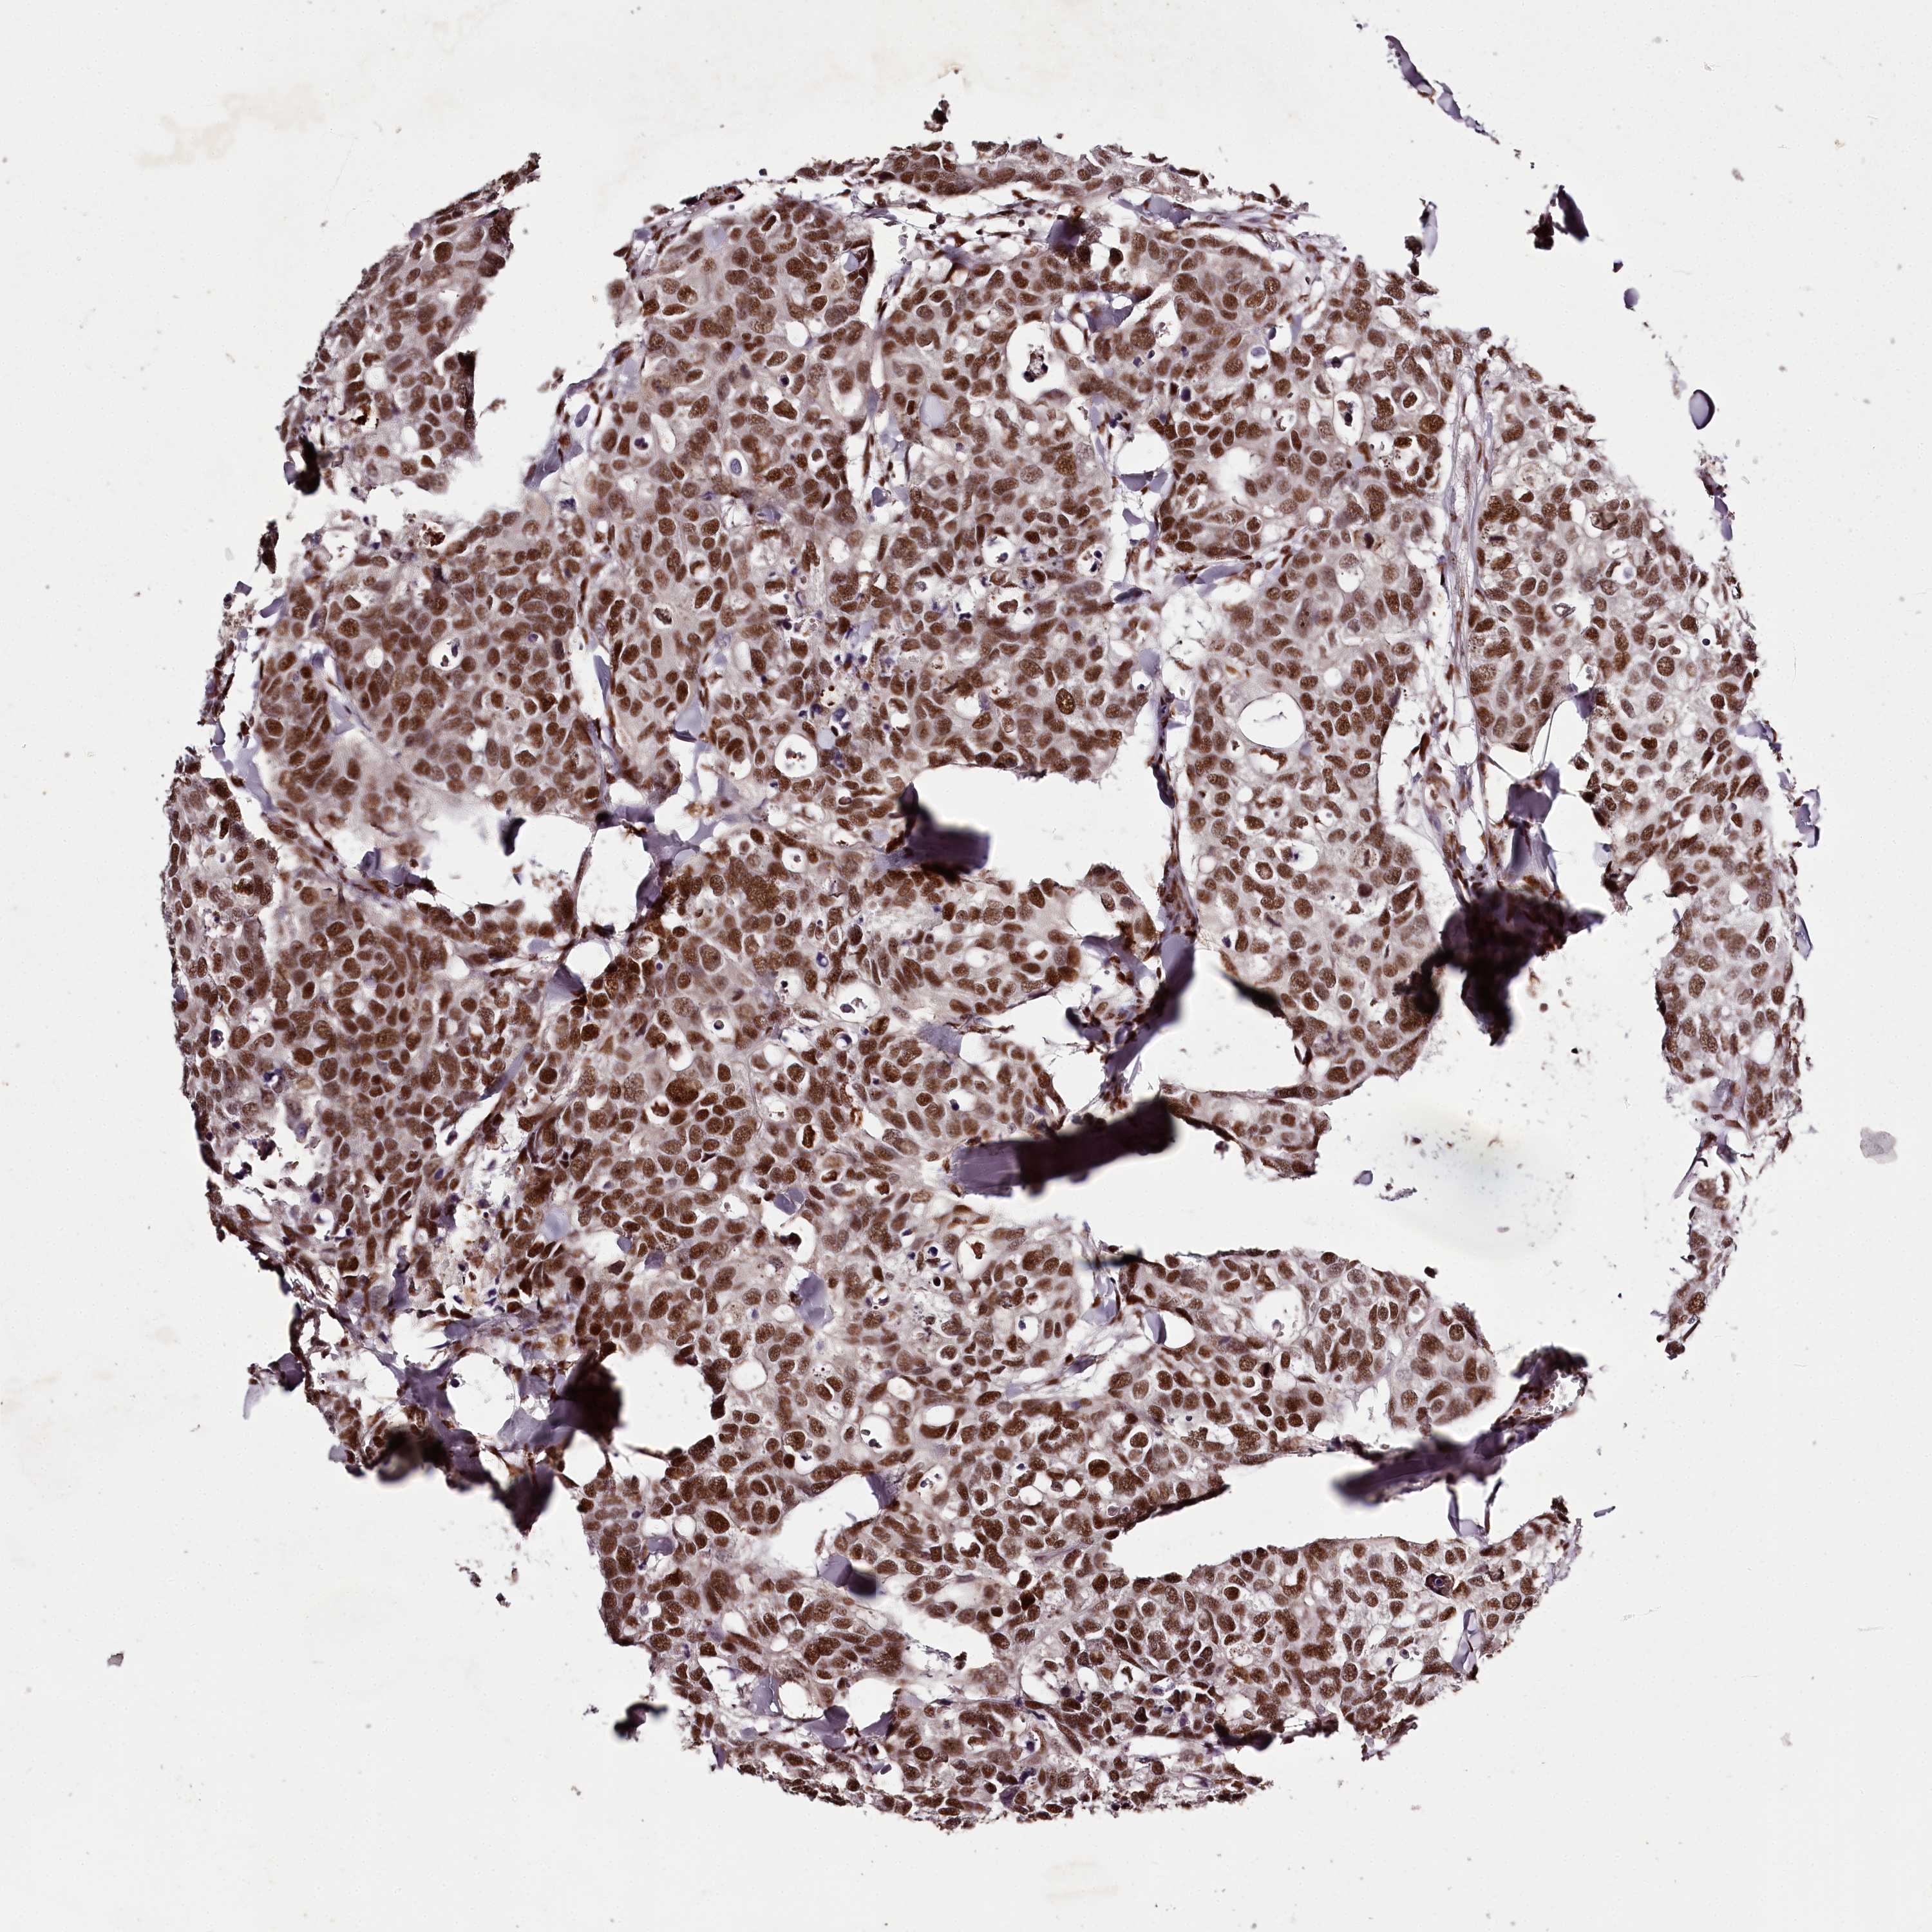

CANCER BREAST CANCER Show tissue menu

BRCA TCGA BRCA VALIDATION PROTEIN EXPRESSION